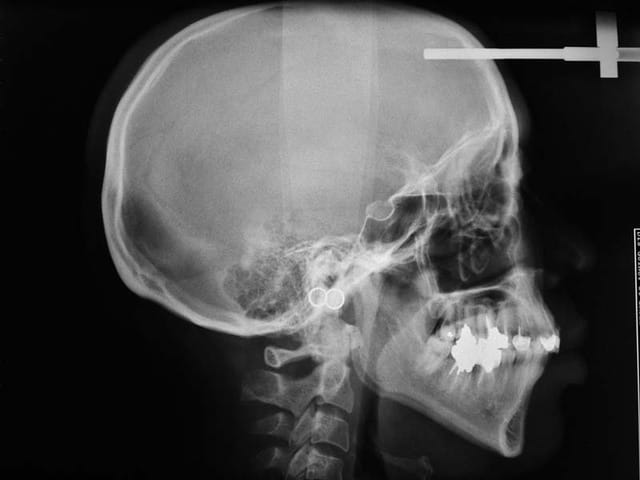

Puisque vous insistez tant :

Voici les Rx. du cas adulte. Pour les photos, ce sera un peu plus tard.

Profil cknevk - Eugenol

D’après l’aspect cutané du visage qu’on devine sur le téléprofil, il ne semble pas que cela soit une caucasienne. Les références habituelles sont donc faussées.

bjc, je comprends mieux pourquoi tu méprises les analyses céphalométriques habituelles : elles ne sont pas toujours adaptées aux patients que tu traites là où tu es.

Ce qui entraîne que même si tu y arrive ici, ce cas ne peut servir de référence valable pour affirmer qu’on peut tout traiter sans avulsion…